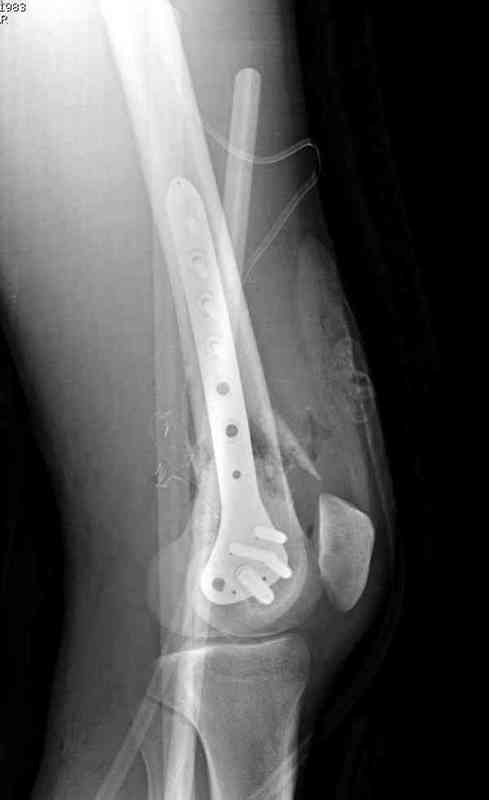

Пострадавшему 23, пистолетная огнестрельная не кроветочащая рана, меньше одного см диаметром, входное отверстие расположено латерально, и выход передне-медиально, и еще имеется второе пулевое ранение правой navicular bone с этой стороны.

Несмотря на сниженный до 0.9 BI-ankle-brachial-index (обязательное, недорогое исследование при подозрении на повреждение сосудов, рассчитанный по разнице давления в нижней и верхней конечности), последующее КТ ангиограмма не подтвердила повреждения артериальных сосудов.

Доступ был латеральный, при вскрытии с задней

поверхности бедра обнаружили кровотечение. Поднятием давления на заранее установленном турникете на конечности проконтролировали кровотечение.

В данном случае мы не ставили осуществление гемостаза приоритетным, после 30 минут больной оставлен вызванному сосудистому хирургу со стабильной фиксацией бедра. Несмотря на выбранный передне-медиальный доступ, хирург произвел восстановление сосудистого повреждения.

При близости сосудов к многооскольчатому повреждению костей, сперва необходимо удостовериться в наличии повреждения сосудов без применения турникета.

Сосудистые повреждения часто приводят к увеличению

давления в компартментах, мониторинг на голени показал увеличение, и поэтому сделана профилактическая латеральная фасциотомия.

Латерально пластину защитили ушиванием

илио-тибиального тракта, а медиальная сторона была ушита мышцей, и все раны закрыли ваккумированием (VAC)

На третий день после Irrigation & Debridment закрыли все раны за исключением компартментальной раны из-за отека, медиально в дефект кости установили Putty Grafton Bone Substitute. На компартментальную рану вакуум и мероприятия по сближению краев раны резиновой стяжкой.

На 9й день с момента травмы ушили рану без натяжения. Больной получает реабилитацию, движения коленного сустава с помощи CPM-continuous passive motion machine. Сегодня выписан.